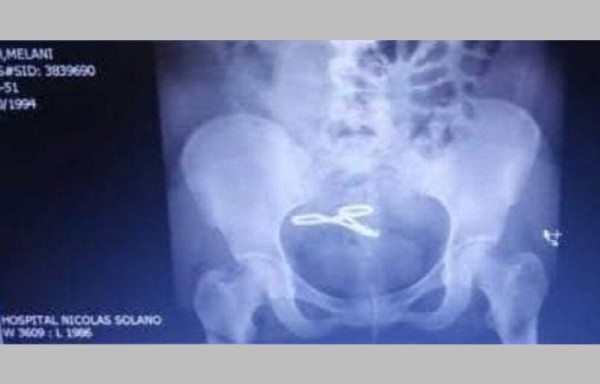

Mientras que Elzebir Montenegro perdió a su hija Sofía Victoria Bordones el 12 de abril del año 2017, por una supuesta negligencia médica; Melanie Smith, el día que trajo al mundo a su pequeña, Nathali, le dejaron una pinza en sus entrañas.

Smith, quien tiene 27 años, contó que el pasado lunes, a pesar de su calvario y de las pruebas que tiene, entre ellas un ultrasonido donde se ve claramente la pinza alojada en su interior), el falló de su caso no fue favorable porque el juez considera que está fuera del rango para que el caso proceda. Es decir, el caso quedo prescrito.

‘En el 2018, por el sangrado me iban a hacer una transfusión para hospitalizarme y antes de eso me realizaron un ultrasonido (ver foto).

La joven madre fue traslada inmediatamente al HST donde los doctores le iban a hacer una cirugía rápida pero sin informarle por qué la iban a abrir. Ella desconocía lo que arrojó el ultrasonido. Luego de horas se enteró de que tenía una pinza. Fue operada, pero al haber pasado años el instrumento se adhirió al intestino delgado y le tuvieron que extirpar una gran parte.

‘Me cortaron 21 centímetros de intestino' lamentó la ciudadana. Ella recordó que en septiembre del 2019 acudió la Fiscalía en Calidonia para denunciar esta negligencia que la tiene medicada de por vida y sin la posibilidad de tener más hijos.